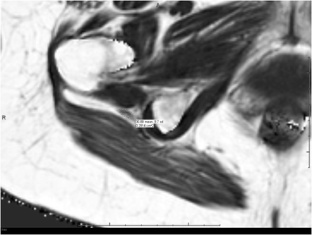

Fig. 1

63-year-old with right buttock pain and sciatica for two years, suspected piriformis syndrome. Axial T2 SPAIR (A) image shows asymmetrically hyperintense right sciatic nerve, even better identified on diffusion image (B). On mDixon quant image (C), notice increased fat fraction of the right sciatic nerve vs left (31.5% vs 27.6%) as well as increased nerve area (0.27 vs 0.25cm2). (GIF 6 kb)